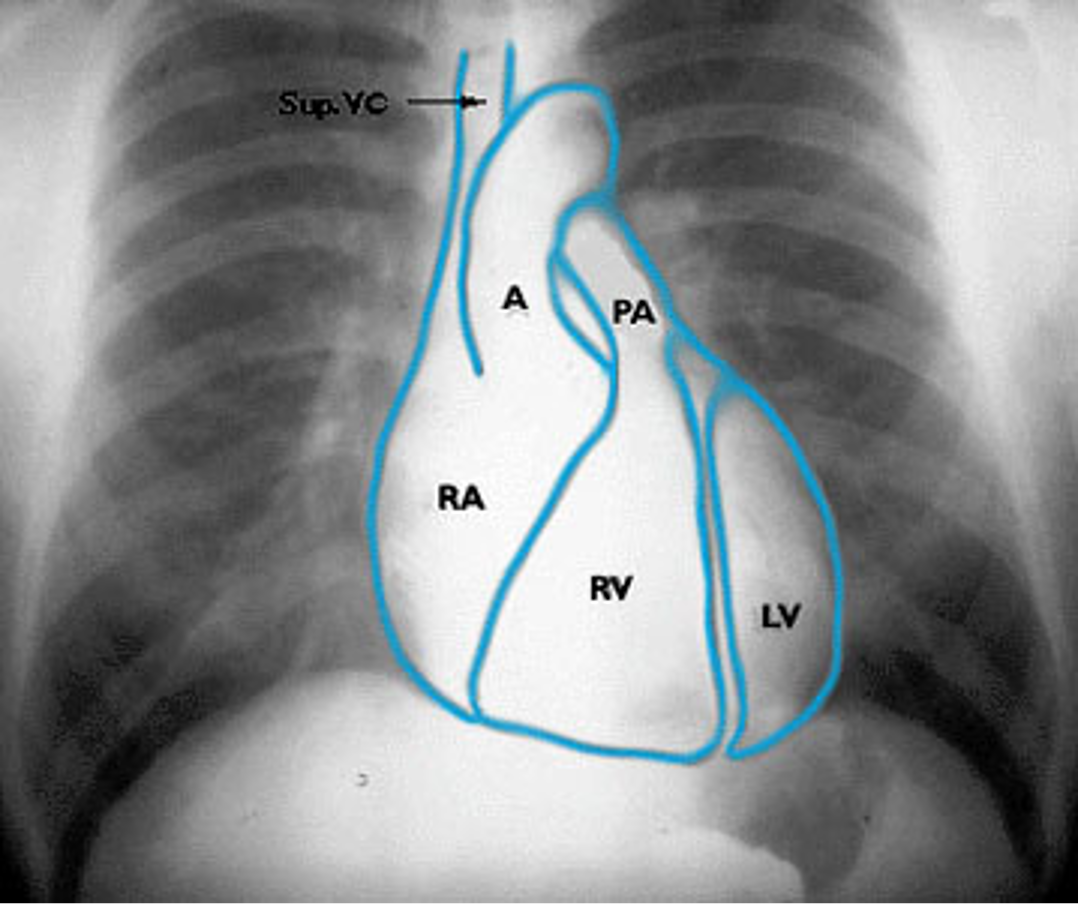

Which 3 mediastinal vessels are visible on the right side in mediastinal imaging?

brachiocephalic vessels

azygos vein

ascending aorta

Name the mediastinal contours according to the numbers

1- superior vena cava

2- right atrium

3- inferior vena cava

4- aortic arch or knob

5- left pulmonary trunk

6- left pulmonary artery

7- left atrium

8- left ventricle

9- left cardiophrenic angle

Name the structures according to number